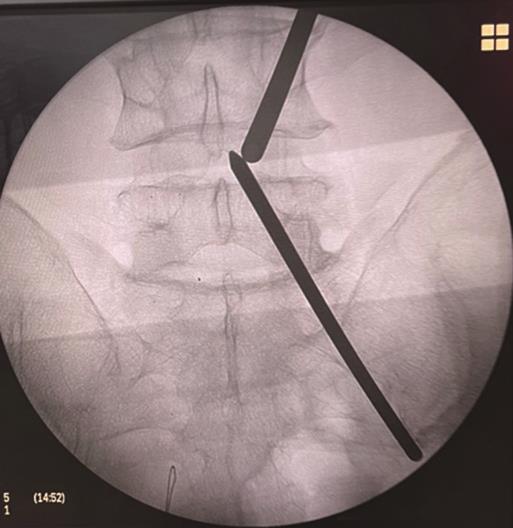

• 3种骶2髂骨螺钉置钉技术准确性的比较研究

2023, 48(11):1381-1386. DOI: 10.13406/j.cnki.cyxb.003371

摘要 (66) HTML (38) PDF 1.13 M (179) 评论 (0) 收藏

摘要:目的 比较传统徒手置钉,3D打印模板引导技术(three-dimensional printed template guided technique,TGT)和ball tip置钉技术在置入骶2髂骨(s2 alar-iliac,S2AI)螺钉的准确性。方法 回顾分析接受S2AI螺钉放置的145例患者,按置钉技术不同将其分为徒手技术组(36例)、TGT技术组(48例)和ball tip技术组(61例)。所有患者术前行骨盆CT确认最佳S2AI螺钉的最佳轨道参数,术后CT扫描评估螺钉轨迹的准确性,比较3种技术的置钉准确性。结果 3组患者S2AI螺钉的最佳轨道参数差异均无统计学意义(P>0.05);3组患者共置入S2AI螺钉290枚。其中,传统徒手技术组72枚,TGT技术组96枚,ball tip技术组122枚。传统徒手组置钉不准确率为18.1%(13/72),TGT技术组置钉不准确率3.1%(3/96),ball tip组置钉不准确率为4.1%(5/122):TGT技术组置钉准确性高于传统徒手技术组,差异有统计学意义(P<0.05);ball tip技术组置钉准确性也高于传统徒手技术组,差异有统计学意义(P<0.05);TGT技术组置钉准确性虽高于ball tip技术组,但差异无统计学意义(P>0.05)。结论 TGT技术和ball tip技术均为S2AI螺钉置入的可靠技术,二者的准确性均明显高于徒手技术,但ball tip技术操作简单。

• 0+1

• 1+1